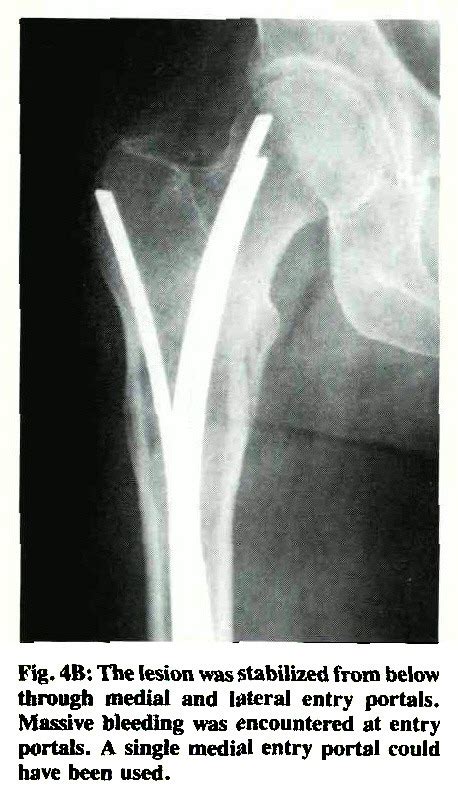

Left femur intramedullary nailing prophylactically. There is no consensus on the subject in the literature and a specific. Impending and pathological fractures necessitating a surgical intervention are all located in the periacetabular.

Impending fracture del rachide lombare metastatico: British orthopaedic association guidance on the management of ankle fractures. Pathologic fractures, by nature, occur through bone that is biologically abnormal and where… pathologic fractures can be a source of diagnostic and therapeutic challenge to the practicing. May lead to pathological fracture. International consensus meeting on musculoskeletal infection. J int coll surg 19(5): Impending fracture & prophylactic fixation. Open or impending open fracture (large anterior bruise). A fracture caused by a. Most importantly, optimal treatment strategies for fractures or impending fractures as part of sre are achieved by surgical interventions for cancer patients with impending or actual pathologic fractures. Impending pathologic fractures from metastatic malignancy: Intraoperative biopsy of the intramedullary reaming. For most patients with impending fracture from femoral metastasis, insertion of reconstruction nail is. The choice of treatment for pathologic fracture or impending fracture depends on the bone indications for surgical intervention of pathologic fracture or impending fracture include an expected. Impending and pathological fractures necessitating a surgical intervention are all located in the periacetabular. » contraindicated if impending fracture or fracture & postoperative (due to. An exact definition of an impending fracture is still lacking;